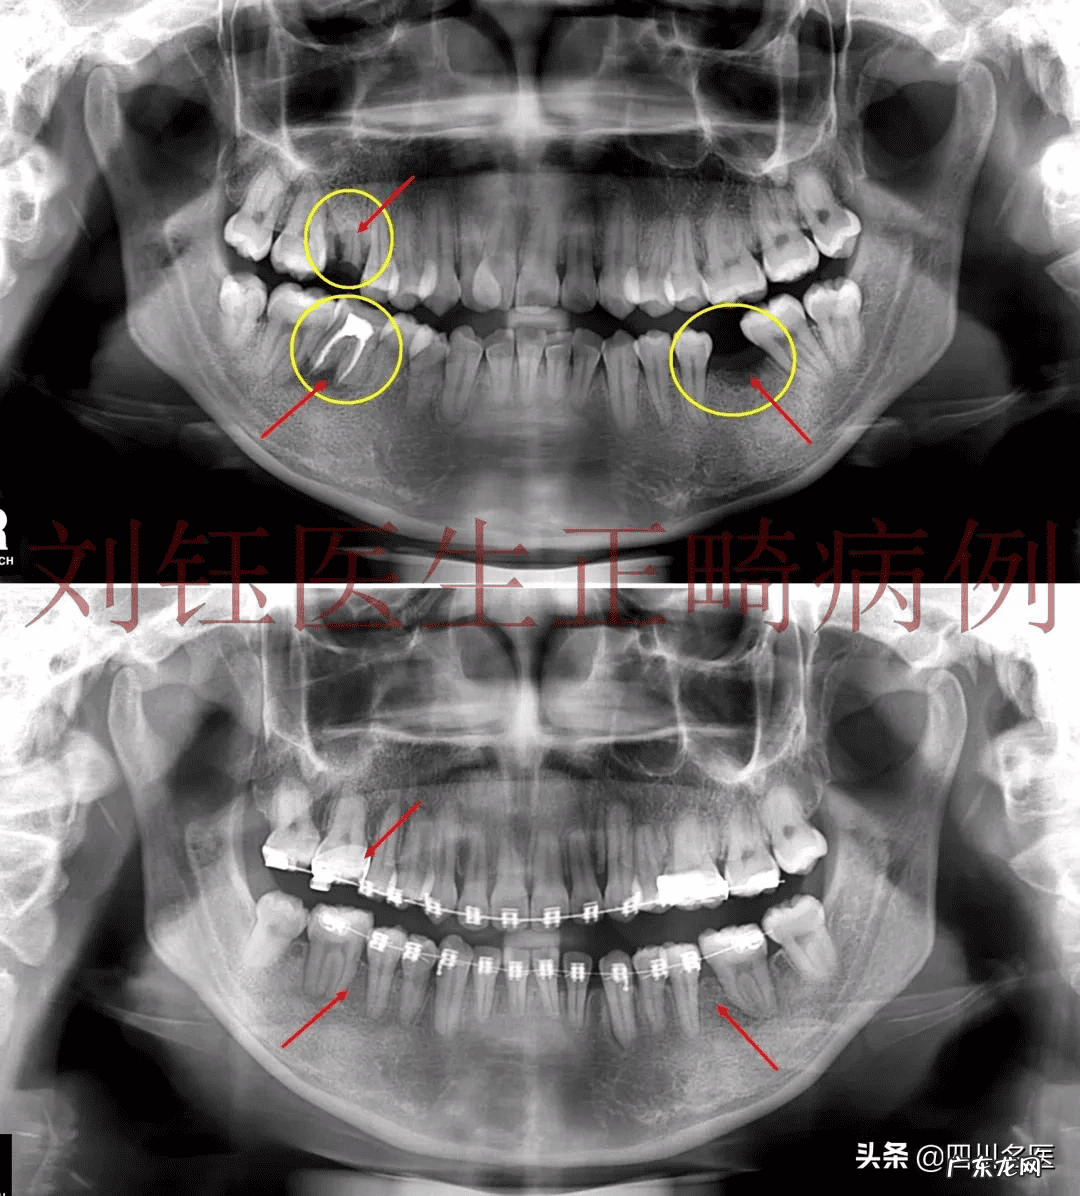

文章插图

牙齿“搬运”前后对比